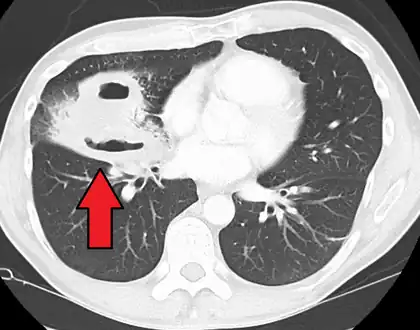

Lung abscesses are often on one side and single involving posterior segments of the upper lobes and the apical segments of the lower lobes as these areas are gravity dependent when lying down. Presence of air-fluid levels implies rupture into the bronchial tree or rarely growth of gas forming organism.

Pulmonary abscess on CT scan